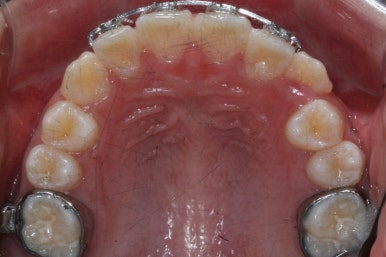

8개월이 지난 모습입니다.

장치는 앞니 4개 + 헤드기어만 사실상 했습니다. 송곳니에는 아무것도 하지 않았죠.

덧니의 변화된 모습이 느껴지시나요?

다시 한 번 말씀드리면 공간확보만 된다면 서서히 좋아지게 됩니다. 100%는 아니기 때문에 추후에 전체적으로 정리를 해줄 필요가 있는데 미리 이렇게 해두면 훨씬 추후에 작업이 간소해지죠.